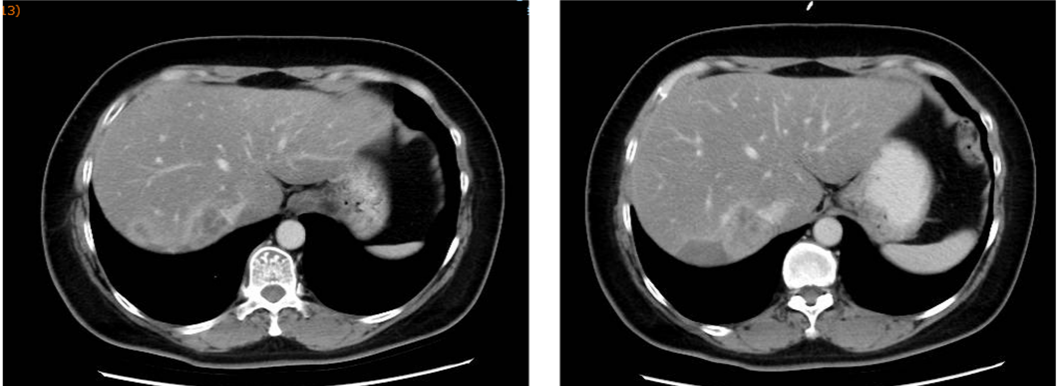

▌二线治疗:

于2015-12-18至2016-05行EC化疗6周期,具体:表柔比星90mg/m2 150mg,环磷酰胺600mg/m2 1000mg d1,Q21d。最佳评效:缩小的SD,2016-5-16改为卡培他滨维持治疗6月,具体:卡培他滨 1.5g bid d1-d14,q21d(1月后因周身不适减量至1.0g bid)。2016-11复查出现新发肝转移,评效PD。PFS为11月。

图3. 二线治疗